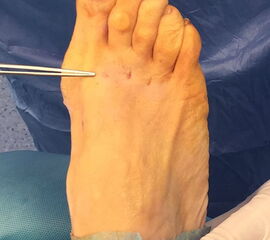

Zum Lesen der Bildbeschreibung und zur Vollansicht bitte die Bilder anklicken.